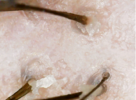

since i was 19 i was loosing my hair with a white bulb at the end of it. About a year and a half ago I went to the dermatologist about my hair loss. She checks my hair with a otoscope for about 10 seconds and does a pull test and tells me i have alopecia and dandruff. Then i tell her that hairs that fall have this white bulb at the end of it and its been going on since i was 19 tells me that i have telogen effluvium. then i get prescribed finasteride, ketoconazole 2% shampoo, and minoxidil 7%. Now 23 still use finasteride, ketoconazole 2% shampoo but not minoxidil 7% it irritated my scalp did use minoxidil 5% but stop after 5 months saw no improvements. About 3 month still loosing lots of hairs but do see less falling and its been going like that since then but recently i started loosing lots of hair again. I'm pretty sure I have chronic telogen effluvium (my scalp is very visible when wet and oily) but I also think I'm loosing my hair because of sebum. My hair gets oily through out the day and after I sleep and wake up I'm just covered in oil I do shower every morning. After I shower I let my hair dry and I comb it and there's just tons of hairs falling out nothing new but now its lots more. I'm posting pictures of my scalp and the white bulb if anybody has any ideas what's going on on my scalp.